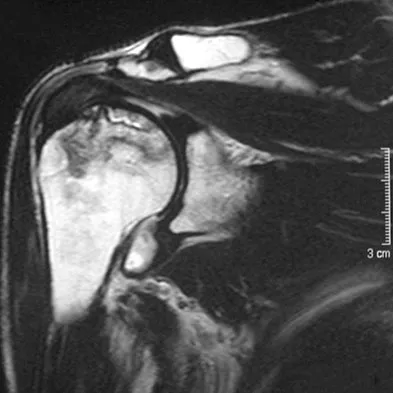

A 72-year-old woman who fell on her right shoulder while using a treadmill is now unable to elevate her right arm. An MRI scan is shown in Figure 7. What is the most likely diagnosis?

The MRI scan reveals a large chronic rotator cuff tear with retraction and fatty infiltration atrophy of the supraspinatus and infraspinatus tendons. This tear is responsible for the patient's severe weakness and inability to elevate the arm.